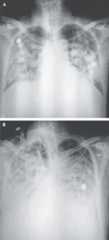

Three adult patients presented with severe pneumonia and were admitted to a hospital in Wuhan on December 27, 2019. Patient 1 was a 49-year-old woman, Patient 2 was a 61-year-old man, and Patient 3 was a 32-year-old man. Clinical profiles were available for Patients 1 and 2. Patient 1 reported having no underlying chronic medical conditions but reported fever (temperature, 37°C to 38°C) and cough with chest discomfort on December 23, 2019. Four days after the onset of illness, her cough and chest discomfort worsened, but the fever was reduced; a diagnosis of pneumonia was based on computed tomographic (CT) scan. Her occupation was retailer in the seafood wholesale market. Patient 2 initially reported fever and cough on December 20, 2019; respiratory distress developed 7 days after the onset of illness and worsened over the next 2 days (see chest radiographs,Figure 1), at which time mechanical ventilation was started. He had been a frequent visitor to the seafood wholesale market. Patients 1 and 3 recovered and were discharged from the hospital on January 16, 2020. Patient 2 died on January 9, 2020. No biopsy specimens were obtained.

Figure 1. Chest Radiographs.

Shown are chest radiographs from Patient 2 on days 8 and 11 after the onset of illness. The trachea was intubated and mechanical ventilation instituted in the period between the acquisition of the two images. Bilateral fluffy opacities are present in both images but are increased in density, profusion, and confluence in the second image; these changes are most marked in the lower lung fields. Changes consistent with the accumulation of pleural liquid are also visible in the second image.